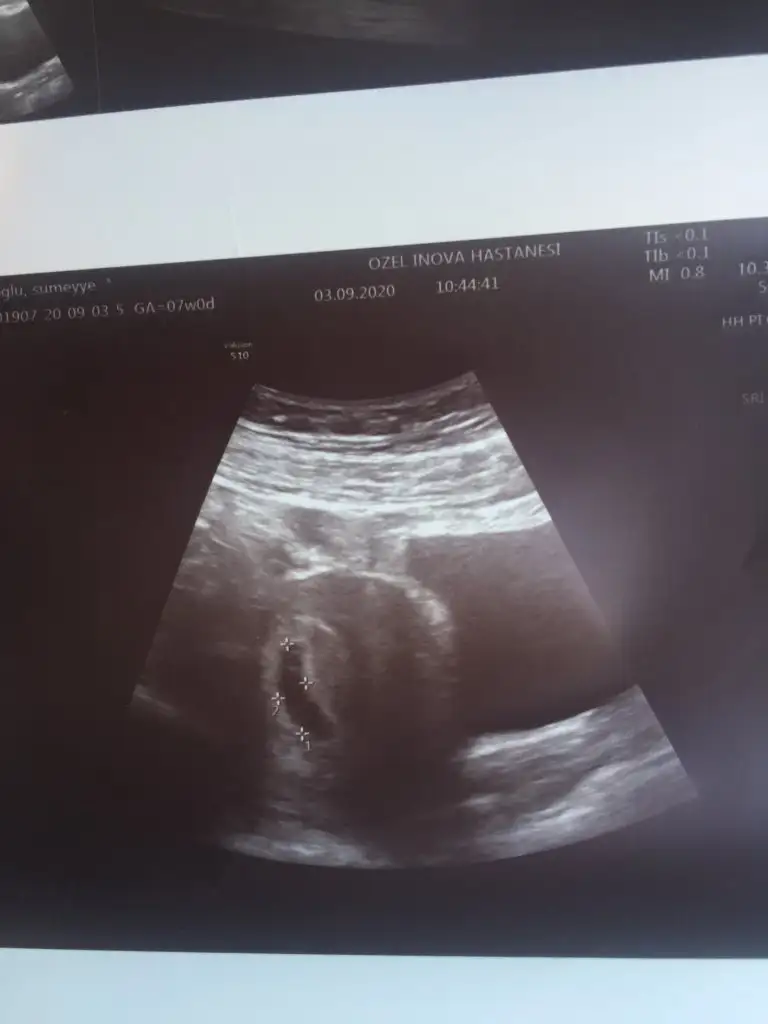

Sonunda bebeği gördük ve kalp atışını duyduk

6+1 görünüyor haftası ama aslında şuan 6+4 üm. 8.haftalardan sonra asıl doğru ölçüm yapılır dedi doktorum.

Darısı tüm kalp atışı bekleyenlerin başına

Bir daha kontrol 3 hafta sonra![]()